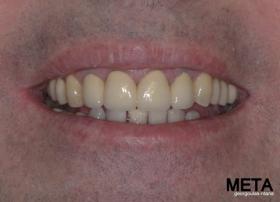

ΠΡΟΣΘΕΤΙΚΗ ΑΠΟΚΑΤΑΣΤΑΣΗ ΣΤΗΝ ΑΝΩ Κ ΚΑΤΩ ΓΝΑΘΟ ΚΑΙ ΤΟΠΟΘΕΤΗΣΗ ΕΜΦΥΤΕΥΜΑΤΩΝ ΜΕ ΚΛΕΙΣΤΗ ΑΝΥΨΩΣΗ ΙΓΜΟΡΕΙΟΥ

Ο ασθενής  προσήλθε στο ιατρείο μας θέλοντας να βελτιώσει την εμφάνιση των πρόσθιων δοντιών του και να αποκαταστήσει την υγεία κ την λειτουργία όλου του στόματος. Πραγματοποιήθηκε περιοδοντική θεραπεία κ ενδοδοντικές θεραπείες (απονευρώσεις) όπου κρίθηκε απαραίτητο και στη συνέχεια τοποθετήθηκαν 3 εμφυτεύματα, 2 δεξιά στις θέσεις του πρώτου κ δεύτερου γομφίου κ 1 αριστερά στη θέση του πρώτου προγομφίου. Κατά την  τοποθέτηση των 2 εμφυτευμάτων της δεξιάς πλευράς, πραγματοποιήθηκε κλειστή ανύψωση ιγμορείου με το σύστημα Piezotome-Intralift , τεχνική που εξασφαλίζει τη μικρότερη δυνατή επέμβαση κ τη μικρότερη μετεγχειρητική ταλαιπωρία (minimally invasive), καθώς κ αυξητικους παράγοντες PRF. Σε όλη τη διάρκεια της θεραπείας  ο ασθενής ήταν καλυμμένος τόσο αισθητικά όσο και λειτουργικά με προσωρινές μεταβατικές αποκαταστάσεις. 4 μήνες μετά την  τοποθέτηση των εμφυτευμάτων κ την οστεοενσωμάτωσή τους, ακολούθησε η τοποθέτηση των μόνιμων αποκαταστάσεων.